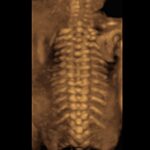

Sistema ecografico per ostetricia, ginecologia e fertilità

VOLUSON S8 con Touch panel

- 3D Uterine Trace

- Immagini veloci chiare e uniformi

- Dettaglio e risoluzione di contrasto eccezionale

- Visualizzazione dei piccoli vasi e dei bordi nel cuore fetale con RadiantFlowTM

- HDlive: tecnologia di rendering 3D/4D di Voluson che trasforma i dati ecografici in immagini più realistiche con profondità, illuminazione e texture migliorate